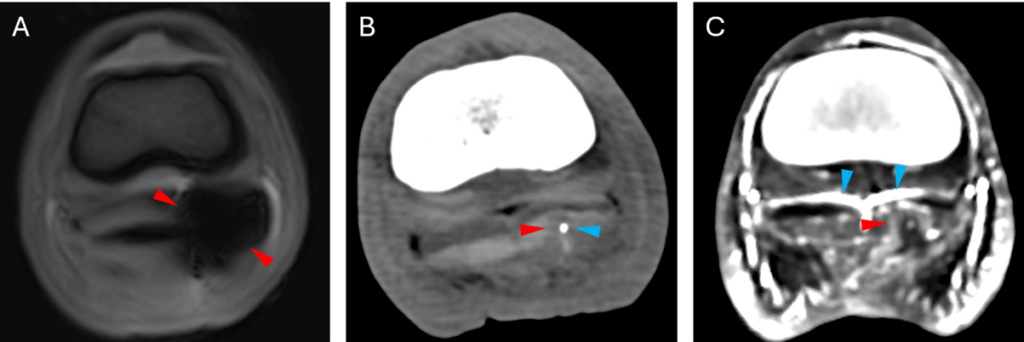

Orthogonal planes allowing the tract to be followed should form part of the MR examination. If the tract is visible, a protocol focusing on the tract can be used, reducing the number of scans required compared to a standard foot study. A T2* sequence and a transverse image plane have been shown to produce the greatest lesion conspicuity (7) and therefore should form part of the imaging protocol. T2* sequences can identify haemorrhage which appears as regions of susceptibility artefact due to haemosiderin causing magnetic field inhomogeneities (7,8) (Figure 2). Gradient recall echo sequences are also advantageous due to their shorter acquisition time compared to spin echo sequences.

MRI can visualise the extent of the penetrating tract and identify the structures involved (10). The tract normally appears as an irregular region of signal void or hypointensity (7) on all sequences extending from the sole (Figures 1 and 2). MR examination of recent injuries (less than one week) is more likely to identify a tract compared to more chronic injuries (7). Reported injuries to the DDFT include linear hyperintensities and core lesions (7). Comparison between surgery and MRI identified correlations in the navicular bursa or in the palmar/plantar border of the DDFT, at the sesamoidean level (7).

Despite its use in tract detection, haemosiderin, as well as residual foreign material, can preclude the identification and or cause distortion of anatomical structures due to susceptibility artefact (1,8). Metallic fragments can remain in a tract despite removal of a penetrating object; this may be detectable radiographically prior to MRI. In such instances, appropriate communication with the owner is important to inform them of potential limitations of the MRI examination. In such instances, CT can be used to visualise the tract (4) and the addition of contrast can aid identification of damage to the DDFT (Figure 3).